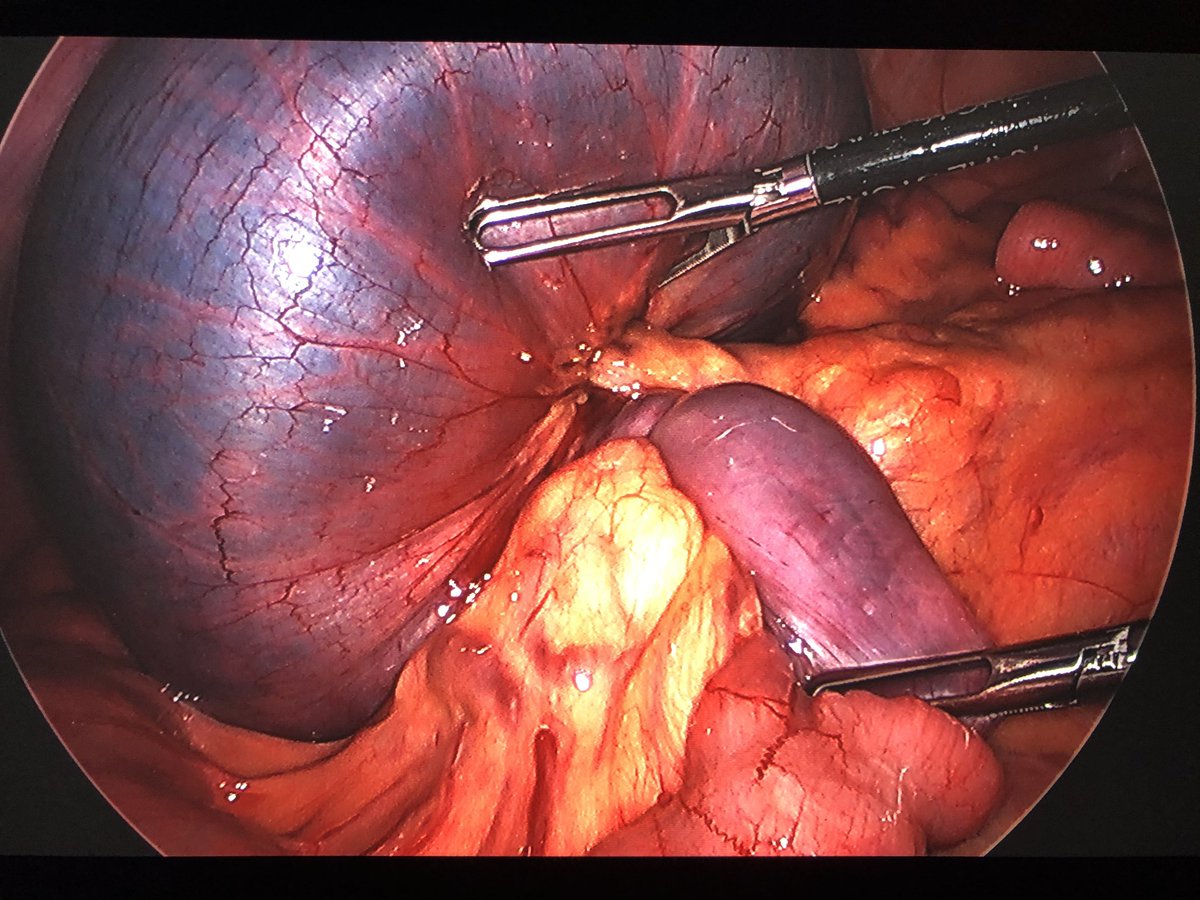

Follow up to yesterday‘s amazing intussusception/volvulus case. Patient did well after surgery. Lead point was a small bowel polyp. Intraoperative picture attached.pic.twitter.com/lAhImacsc6